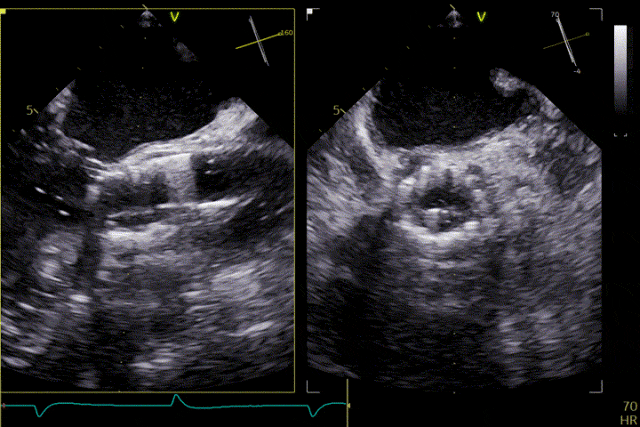

術前超聲

打開定位件

定位件入竇